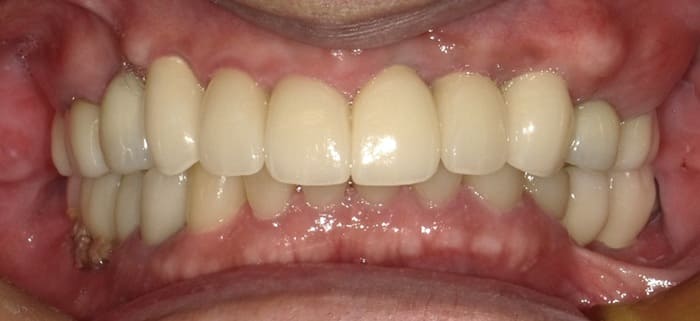

上顎前歯部と両側小臼歯部はインプラント補綴を行い、両側の大臼歯部についても根管治療からやり直して咬合平面を改善すべく補綴を行った。下顎の両側臼歯部に関してもインプラント補綴を行い小臼歯部では根管治療からクラウンによる補綴を行った。左上7番に関しては当初インプラント補綴を行う予定であったがサイナスリフトを伴う治療になることと第一大臼歯までで十分噛めることから埋入せずに経過を見ている。

治療後の口腔内所見である噛み合わせも問題なく機能している。また、一本ずつのインプラント補綴を行ったことでフロスによるケアができ良好な口腔内環境を維持できている。